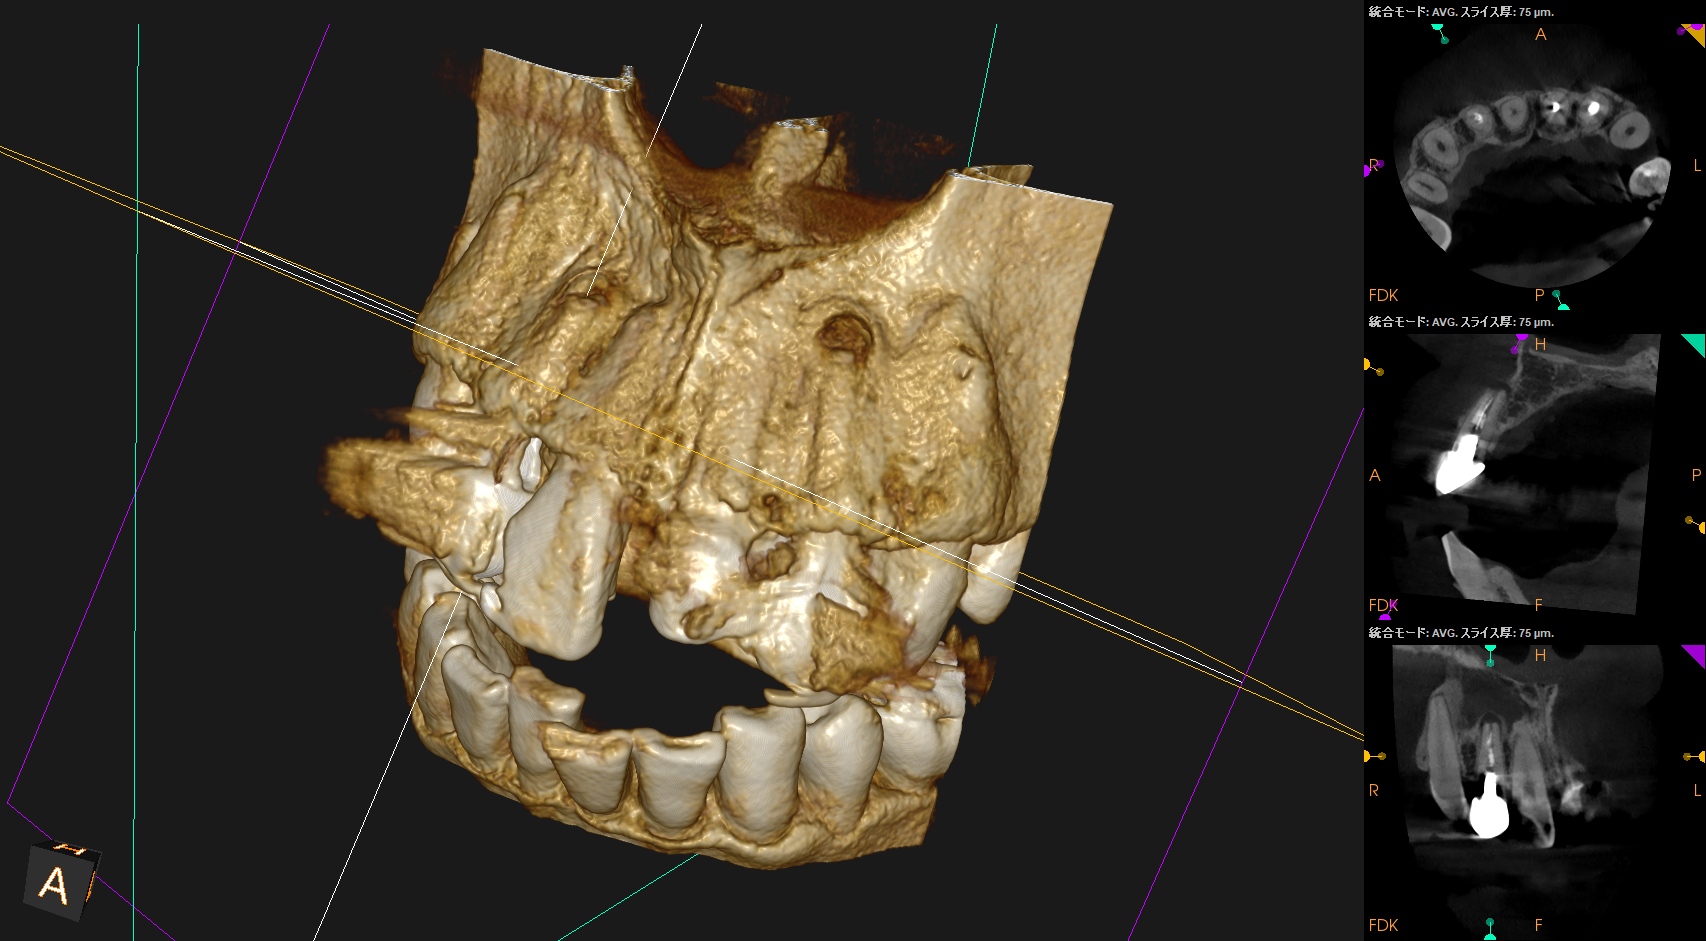

さておき、根充+支台築造後にPA, CBCTを撮影した。

#7

#10